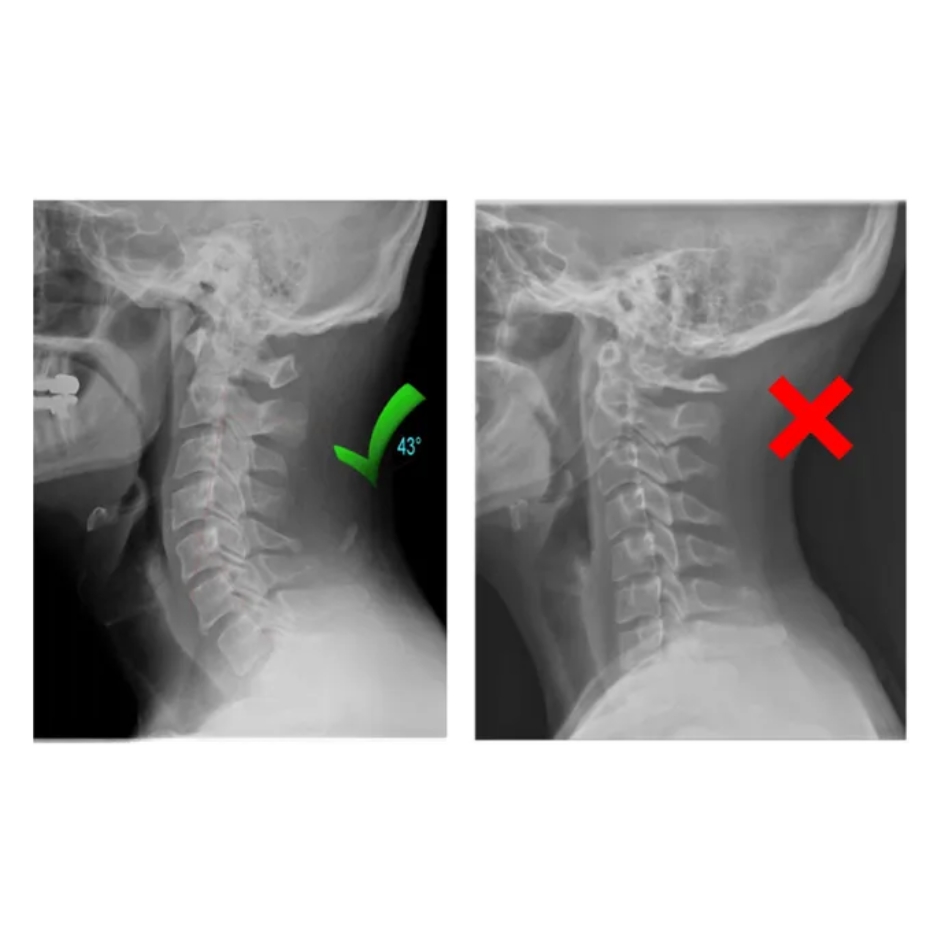

Développé avec des kinés et ingénieurs biomédicaux, NeckCare Flow™ suit des principes d’ergonomie cervicale éprouvés. Matériaux hypoallergéniques, contrôles qualité rigoureux, technologie de traction progressive et diffusion thermique sécurisée : tout est pensé pour une utilisation simple, sûre et efficace à la maison.

Traction cervicale progressive : ouvre l’espace intervertébral sans à-coups.

Soutien ergonomique : respecte la courbure naturelle du cou.